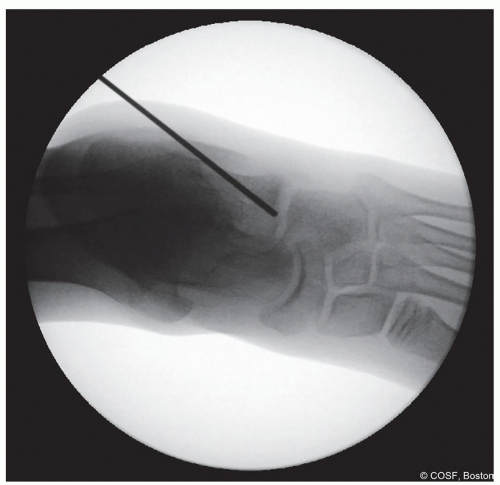

Figure 28-9 ▪ Anteroposterior view fluoroscopy showing the guide pin in the proper location. (Courtesy of Children’s Orthopaedic Surgery Foundation.)